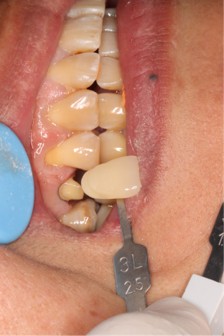

August 1, 2025: Tooth preparation, gingival retraction, shade selection, and impression taking were performed sequentially; the patient tolerated the procedures well